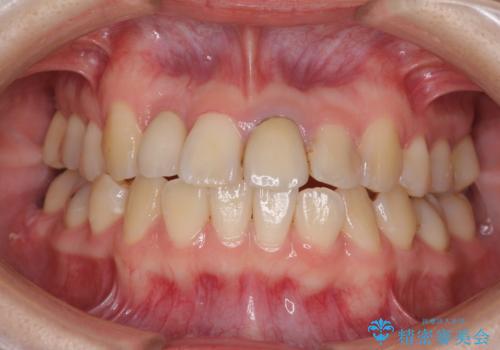

虫歯治療ついでに歯並びの後戻りを改善 インビザラインによる矯正治療

- 奥歯が痛いとのことで来院された患者様です。

上顎親知らず周辺の炎症と、神経組織の失活した歯の炎症による痛みが認められたため、親知らずの抜歯と根管治療を行いました。

根管治療を行った歯はクラウンによる補綴治療が必要となりますが、高校生の頃に行った矯正治療の後戻りも気になるとのことで、補綴治療を行う前に矯正治療を行うこととしました。

後戻りは軽度であり、インビザラインにて歯列を整え、その後にオールセラミッククラウンにて補綴治療を行うこととしました。

ご家庭やお仕事の都合で通院が途絶えた時期があり、治療は長期間となりましたが、無事に終えることができました。